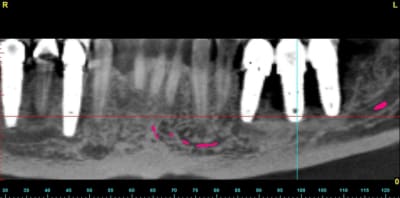

quelques images en 3 D...

un an après !

ça s'arrange pas, voyez plutôt..

augmentation de la perte osseuse +++